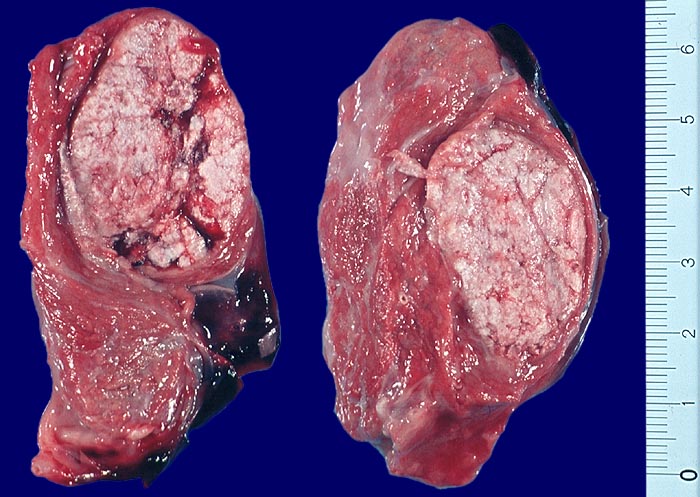

• Anschnitt eines grossen mikrofollikulären Knotens (autonomes Adenom) mit angedeuteter Kapsel und zentraler Einblutung. Oben zwei weitere kleine Satellitenknoten.

Makroskopie